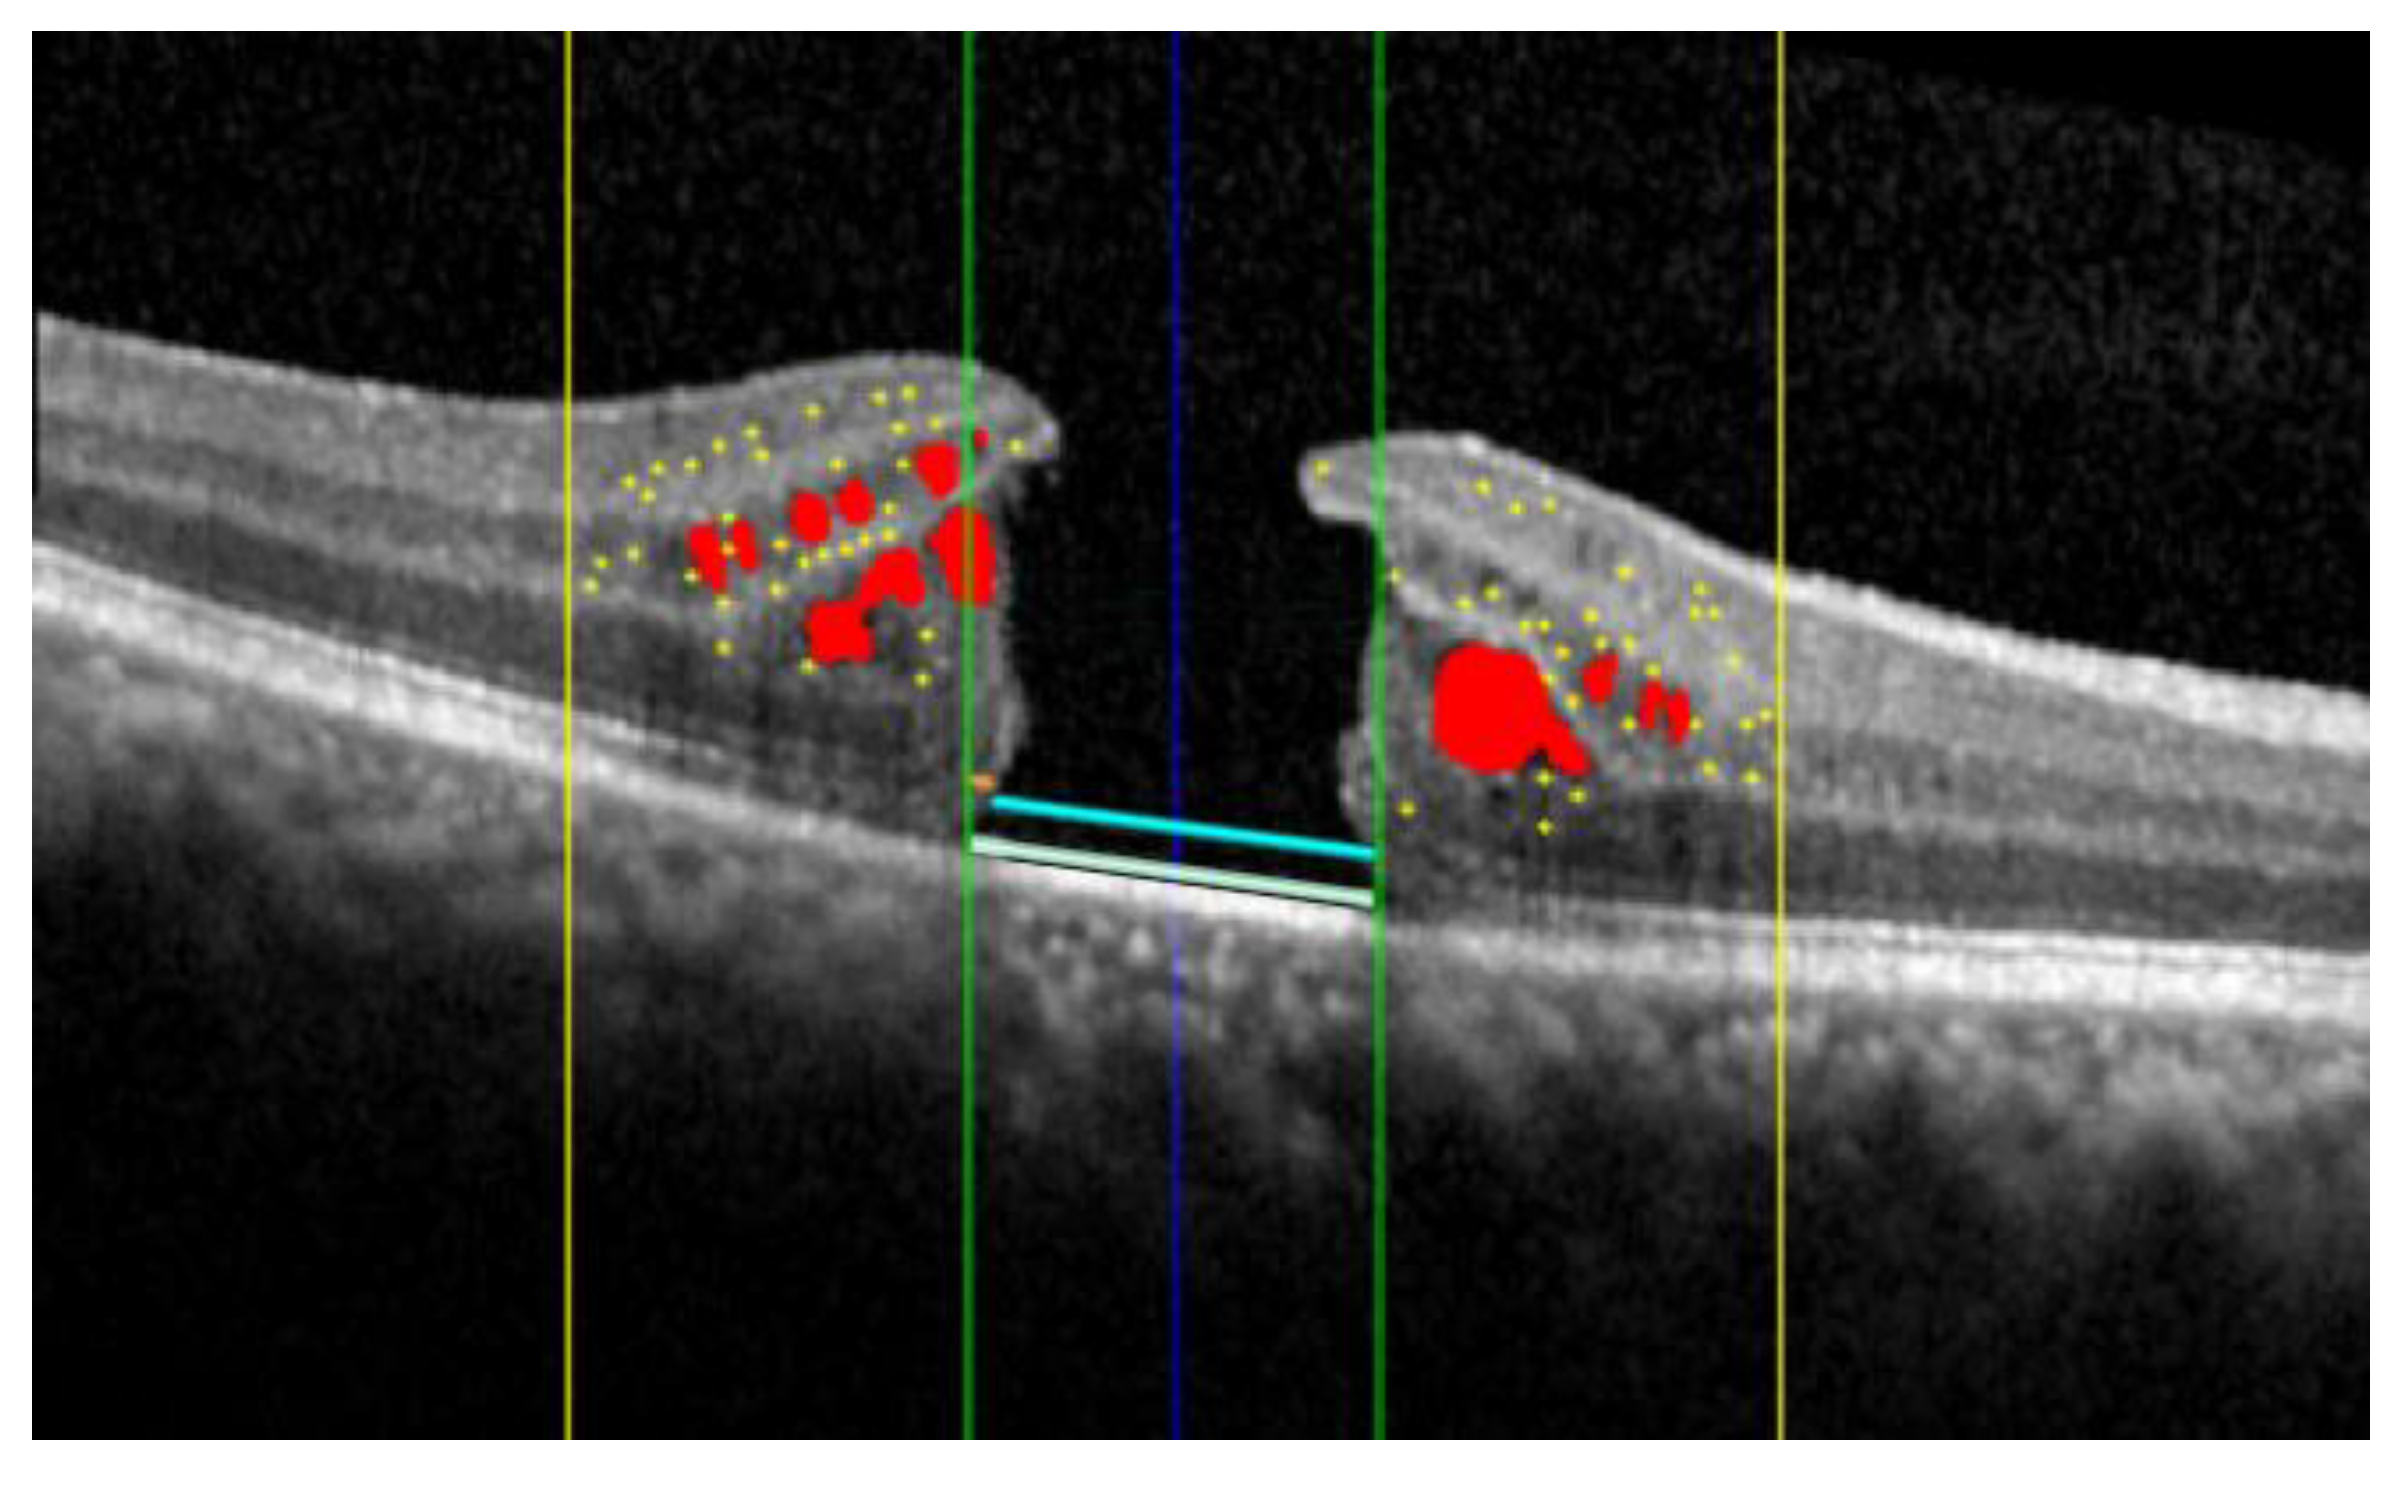

| IRF Volume (mm3) | 0.58 | 0.63 | 0.35 (0.18–0.60) | 0.01 | 0.01 | 0.01 (0.01–0.02) | 0.0001 |

| ELM Interruption (%) | 79 | 18 | 82 (69–94) | 34 | 37 | 12 (0–70) | 0.0006 |

| EZ Interruption (%) | 80 | 22 | 77 (60–99) | 40 | 36 | 46 (17–94) | 0.0007 |